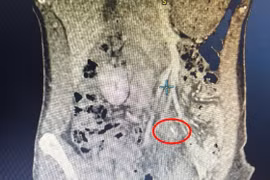

Phát hiện xương cá 5 cm đâm thủng ruột non sau 5 ngày đau bụng

Xương cá là dị vật thường gặp và nhiều người chủ quan. Dị vật có thể xuyên thủng thành dạ dày hoặc ruột, gây áp xe ổ bụng, viêm phúc mạc, nhiễm trùng huyết.